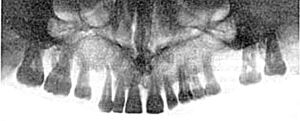

ПАНОРАМНАЯ РЕНТГЕНОГРАФИЯ (рис.1) – методика, позволяющая получить на одной пленке развернутое (несколько увеличенное) изображение одной из челюстей.

Рис.1. Панорамная рентгенограмма верхней челюсти

Для получения изображения применяется рентгеновский аппарат со специальной острофокусной рентгеновской трубкой. Анод рентгеновской трубки во время съемки вводится в полость рта пациента. При съемке верхнего зубного ряда фокус трубки располагают над языком на уровне пятых зубов, для съемки нижнего ряда – в области уздечки под языком. Рентгеновская пленка форматом 18х24 см помещается в гибкую полиэтиленовую кассету с усиливающими экранами высокой разрешающей способности. Во время съемки больной прижимает руками кассету к коже вокруг исследуемой области лица. Если кассета фиксирована неплотно, изображение структуры костей получается нечетким.

Поскольку фокус рентгеновской трубки максимально приближен к объекту исследования, а пленка находится на некотором расстоянии от зубов, обусловленном толщиной мягких тканей, изображение получается увеличенным почти в два раза. Благодаря этому обстоятельству на панорамных снимках различимы мелкие детали, плохо видимые на обычных рентгенограммах.

На панорамных снимках верхней челюсти получается также изображение верхнечелюстных пазух, полости носа, бугров верхней челюсти и скуловых костей. На нижней панорамной рентгенограмме хорошо видны нижнечелюстной канал и основание нижнечелюстной кости. На боковом панорамном снимке одновременно отображаются зубы верхнего и нижнего ряда каждой половины челюсти.

На основании панорамных снимков диагностируют кариес и его осложнения, воспалительные процессы, кисты, новообразования и травматические повреждения челюстей. Однако для оценки степени резорбции межальвеолярных гребней этот метод не пригоден.

Недостатком панорамной рентгенографии является также невозможность контролировать положение во рту аппликатора рентгеновской трубки.

Существенному облучению при этом методе исследования подвергается слизистая оболочка полости рта, поэтому панорамную рентгенографию рекомендуется использовать только при показаниях и не более 1-2 раз в год для каждого пациента. Дополнительная защита при этом виде рентгенографии малоэффективна, т.к. облучению подвергаются органы полости рта, находящиеся вне защитной зоны.

Следует иметь ввиду, что данная методика, в связи с появлением в последние годы более современных способов исследования, используется редко.